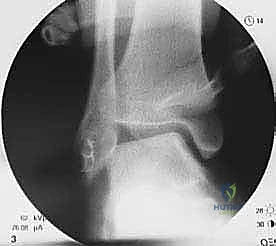

2. التقييم بالمنظار (Arthroscopy) بتقنية 4K:

قبل البدء في إعادة البناء، يقوم الدكتور هطيف بإدخال كاميرا دقيقة جداً (منظار) داخل مفصل الكاحل. تتيح شاشات الـ 4K رؤية تفاصيل المفصل بوضوح مذهل. يتم في هذه الخطوة تنظيف المفصل من أي أنسجة ملتهبة، إزالة الشظايا العظمية أو الغضروفية السائبة، ومعالجة أي تلف في الغضروف ناتج عن عدم الاستقرار المزمن.

4. حفر الأنفاق العظمية:

باستخدام أدوات جراحية دقيقة، يقوم الدكتور هطيف بعمل أنفاق صغيرة جداً في عظم الشظية (Fibula) وعظم الكاحل (Talus) وعظم العقب (Calcaneus). تعتمد هذه الخطوة على المعرفة التشريحية العميقة لضمان وضع الأربطة الجديدة في مسارها التشريحي الطبيعي (Anatomical Reconstruction).